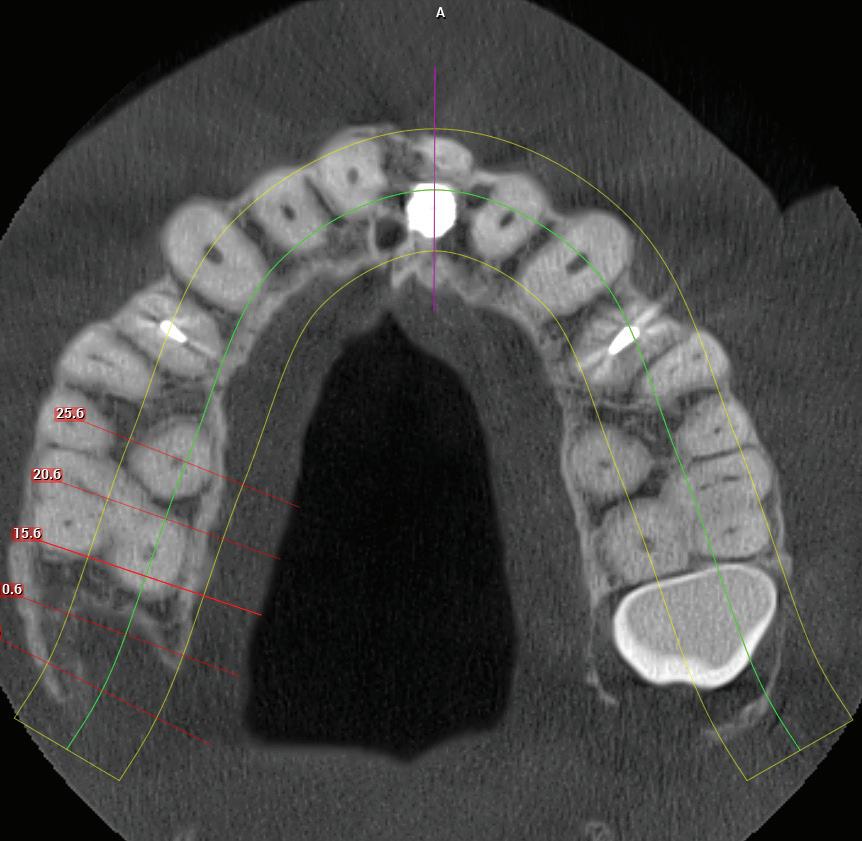

RECONFIGURAREA suportului osos implantar. În cazul prezentat, după ani de terapie ortodontică incorect executată, dezvoltarea dentară a pacientului a complicat obținerea unui zâmbet estetic. S-a reanalizat și s-a optat pentru abordare interdisciplinară care cuprinde chirurgia parodontală, un al doilea tratament

ortodontic și protetica pentru a oferi îngrijirea comprehensivă.

RECUPERAREA planului implantar original. Dacă unul sau mai multe implanturi planificate eșuează, perspectiva reimplantării în locația compromisă poate fi simplificată prin transformarea ghidului chirurgical la nivel osos într-un ghid chirurgical suportat de implanturi în momentul intervenției chirurgicale primare.